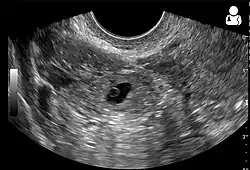

Transvaginal ultrasonography

An ultrasound showing a gestational sac with the fetal heart in the fallopian tube has a very high specificity for ectopic pregnancy. It involves a long, thin transducer, covered with the conducting gel and a plastic/latex sheath and inserted into the vagina.[38] Transvaginal ultrasonography has a sensitivity of at least 90% for ectopic pregnancy.[5] The diagnostic ultrasonographic finding in ectopic pregnancy is an adnexal mass that moves separately from the ovary. In around 60% of cases, it is an inhomogeneous or a noncystic adnexal mass, sometimes known as the "blob sign". It is generally spherical, but a more tubular appearance may be seen in the case of hematosalpinx. This sign has been estimated to have a sensitivity of 84% and a specificity of 99% in diagnosing ectopic pregnancy.[5] In the study estimating these values, the blob sign had a positive predictive value of 96% and a negative predictive value of 95%.[5] The visualization of an empty extrauterine gestational sac is sometimes known as the "bagel sign", and is present in around 20% of cases.[5] In another 20% of cases, there is visualization of a gestational sac containing a yolk sac or an embryo.[5] Ectopic pregnancies where there is visualization of cardiac activity are sometimes termed "viable ectopic".[5]

-

Transvaginal ultrasonography of an ectopic pregnancy, showing the field of view in the following image -

A "blob sign", which consists of the ectopic pregnancy. The ovary is distinguished from it by having follicles, whereof one is visible in the field. This patient had an intrauterine device (IUD) with progestogen, whose cross-section is visible in the field, leaving an ultrasound shadow distally to it. -

Ultrasound image showing an ectopic pregnancy where a gestational sac and fetus have been formed